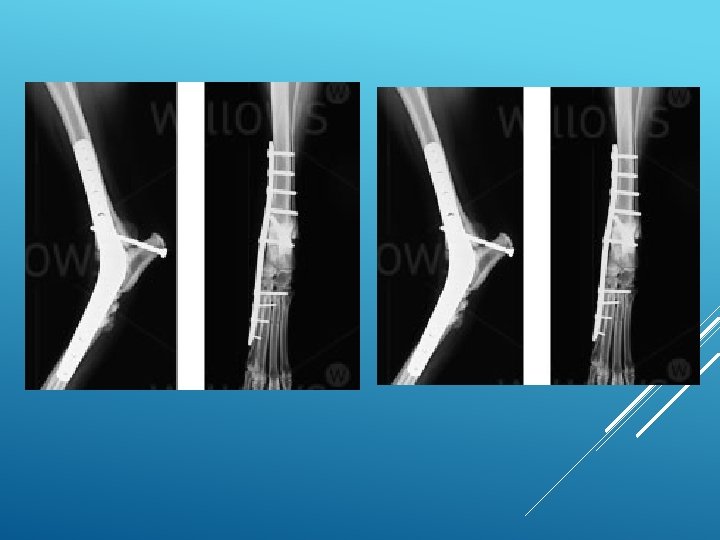

What is arthrodesis? Arthrodesis means the surgical fusion of a joint. In other words, the bones forming the joint are permanently joined together so that there is no movement in this part of the limb. Arthrodesis is a salvage procedure that is generally only performed when there are no other options to save the function of the joint.

What joints can be arthrodesed (fused)? The shoulder, elbow, carpal (wrist), stifle (knee), hock (ankle) and digit (toe) joints can be arthrodesed. The main joint that cannot be fused is the hip joint. This is generally not a problem since the hip joint can be replaced with an artificial one. Elbow and knee replacements are also possible alternatives to arthrodesis of these joints.

There a number of important steps when fusing a joint: the surface of the joint (known as the articular cartilage) must be removed to enable bony fusion. a bone graft should be placed into the spaces between the bones to promote fusion. This may be an autograft (from the patient), an allograft (from a donor) or a combination of both.